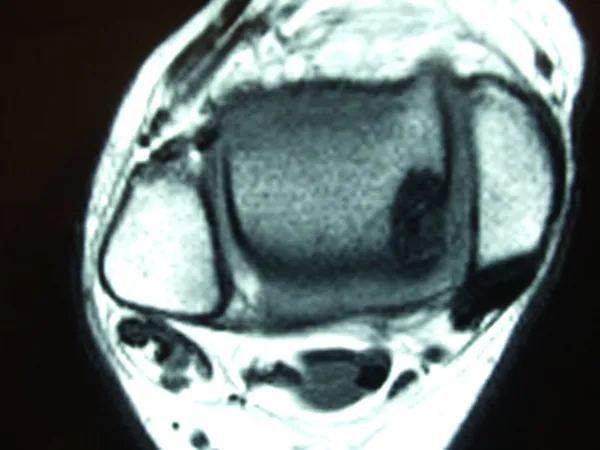

A series of intraop ankle arthroscopy pics of synovial chondromatosis with OCD talus and tibia and microfracture.